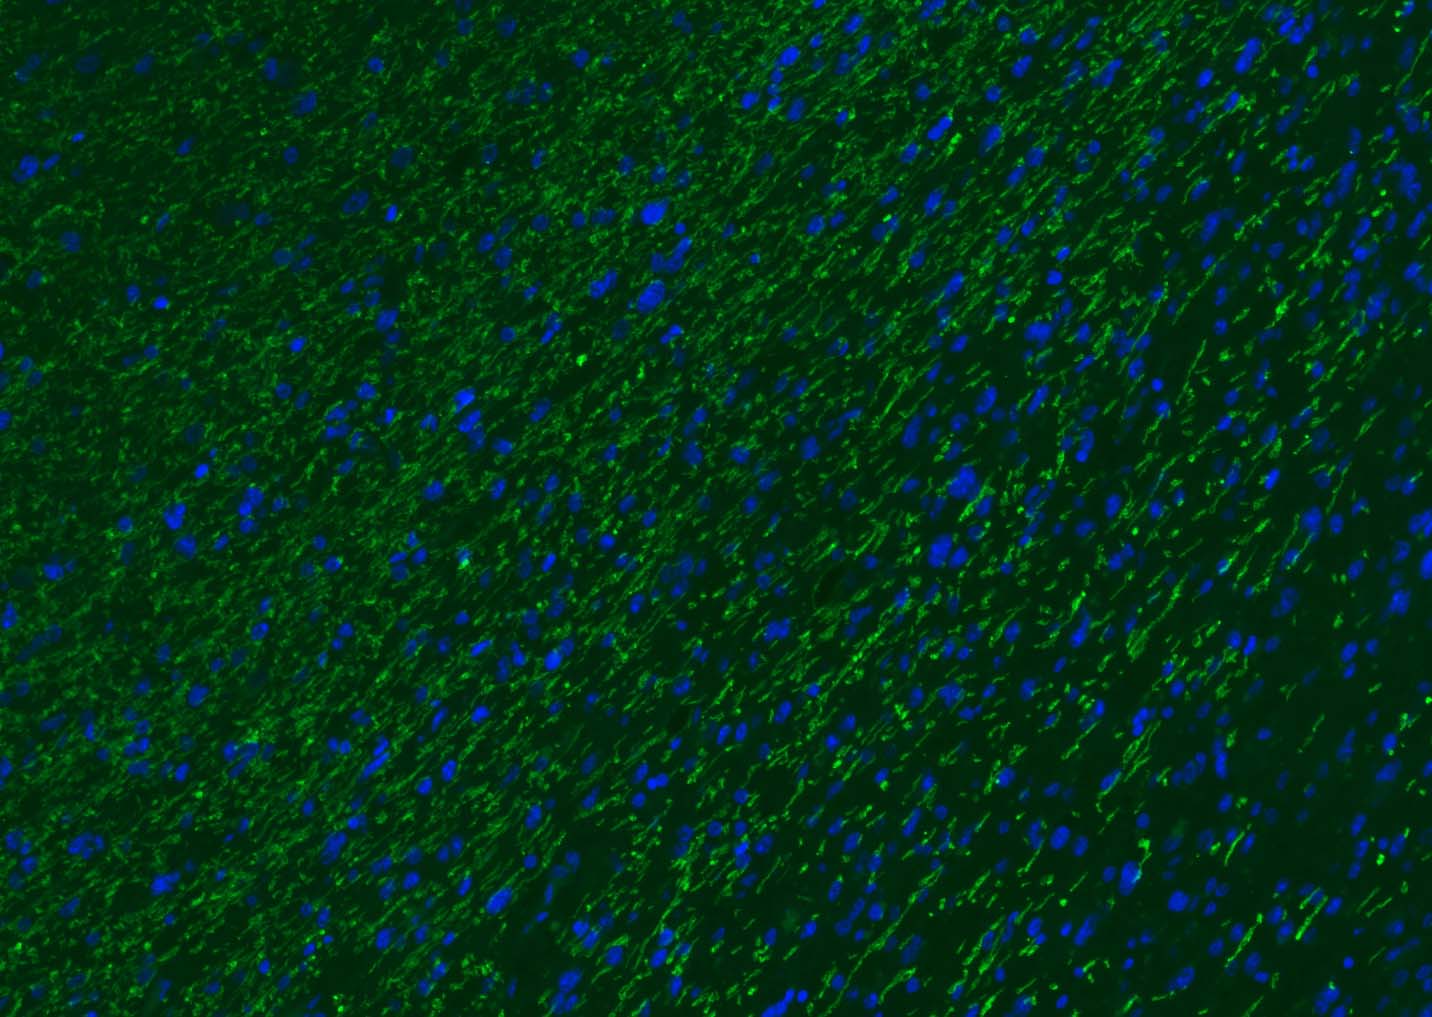

The protein encoded by the classic MBP gene is a major constituent of the myelin sheath of oligodendrocytes and Schwann cells in the nervous system. However, MBP-related transcripts are also present in the bone marrow and the immune system. These mRNAs arise from the long MBP gene (otherwise called "Golli-MBP") that contains 3 additional exons located upstream of the classic MBP exons. Alternative splicing from the Golli and the MBP transcription start sites gives rise to 2 sets of MBP-related transcripts and gene products. The Golli mRNAs contain 3 exons unique to Golli-MBP, spliced in-frame to 1 or more MBP exons. They encode hybrid proteins that have N-terminal Golli aa sequence linked to MBP aa sequence. The second family of transcripts contain only MBP exons and produce the well characterized myelin basic proteins. This complex gene structure is conserved among species suggesting that the MBP transcription unit is an integral part of the Golli transcription unit and that this arrangement is important for the function and/or regulation of these genes.

| 应用 | 已检合格种属 | 预测种属 | 推荐稀释比例 |

|---|---|---|---|

| WB | Mouse, Rat | Human, Rabbit, Pig, Sheep, Cow, Dog, Horse | 1:1000-5000 |

| IHC-P | Human, Mouse, Rat | Rabbit, Pig, Sheep, Cow, Dog, Horse | 1:500-2000 |

| IHC-F | Human, Mouse, Rat | Rabbit, Pig, Sheep, Cow, Dog, Horse | 1:500-2000 |

| IF | Human, Mouse, Rat | Rabbit, Pig, Sheep, Cow, Dog, Horse | 1:500-2000 |

| Flow-Cyt | Rat | Human, Mouse, Rabbit, Pig, Sheep, Cow, Dog, Horse | 1:100-200 |

交叉反应: Human, Mouse, Rat (predicted: Rabbit, Pig, Sheep, Cow, Dog, Horse)